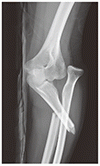

モンテジア骨折

Monteggia Fracture

26 歳の女性が,スケート中に手をついて転倒したあと,左肘の痛みで受診した.X 線写真で,尺骨骨幹部近位 1/3 の骨折と,橈骨頭の後方脱臼が認められた.